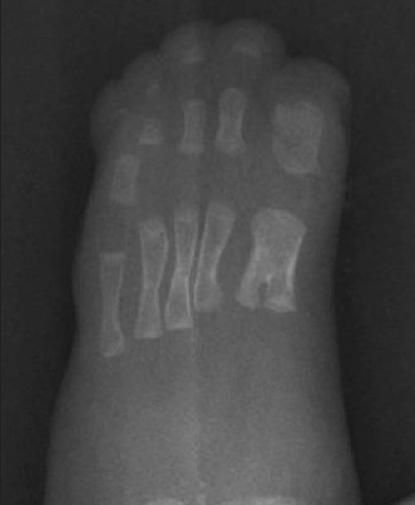

Syndactyly of all 4 extremities is characteristic of Apert syndrome (Figure 2). This finding is typically absent in other craniosynostoses. The term "mitten hand" is frequently used to describe the appearance of the fused soft tissues.

These close-up views of the infant's left hand and left foot show the severewebbing of adjacent digits that was present in all 4 extremities.

A skeletal survey revealed sclerosis in the region of the coronal sutures that confirmed synostosis (Figure 3). Radiographs of the hands demonstrated soft tissue symphalangism with abnormally broad and fused proximal phalanges; several distal phalanges were absent (Figure 4). Radiographs of the feet demonstrated bifid proximal first metatarsals and some hypoplastic proximal phalanges (Figure 5). The infant had a normal spine, 12 paired ribs, and a normal shoulder girdle and pelvis. The long bones of the upper and lower extremities were symmetrical and normally formed.

A radiograph of the left foot showed bifid proximalfirst metatarsals and some hypoplastic proximal phalanges.